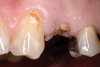

Restorative failure of an existing amalgam restoration on the maxillary left first premolar from recurrent caries is documented here (Figure 2). The periapical radiograph revealed an extensive carious lesion extending into the pulp chamber. After clinical and radiographic evaluation, a treatment plan was discussed with the patient that included endodontic therapy, crown lengthening, and reinforcing the root and supporting the tooth-restorative complex with a fiber-reinforced post and core system.

Fig 2. Restorative failure of an existing amalgam restoration on the maxillary left first premolar from recurrent caries.

Figure 2